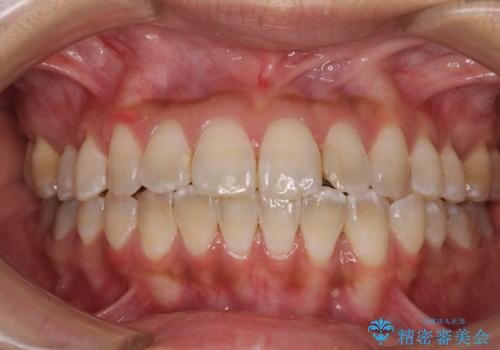

【ワイヤー矯正】八重歯 歯のでこぼこを治したい!